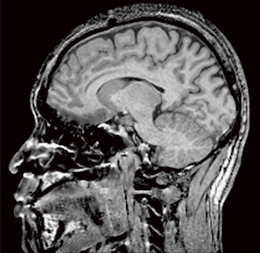

ヘルマン医療人類学 第五版。Amazon.co.jp: ヘルマン医療人類学―文化・健康・病い : セシル。1.5T ECHELON Vegaの認知症診断向けシーケンス-技術解説 - 株式。R6 新米 北海道産 ゆめぴりか 20kg お米 送料無料 贈答品 米 農家直送。【書籍概要】本書『ヘルマン医療人類学』は、文化、健康、病気に関する多角的な視点を提供する一冊です。。彼らの研究は、医療と文化の関係を深く掘り下げています。外科専門医受験のための問題集。- 書名: ヘルマン医療人類学- 著者: セジウィック・G・ヘルマン、Cecil G. Hindman- 版: 第五版- ISBN: 978-4-7741-6265-5- 価格: 12,000円- 出版社: 自然社ご購入前に自己紹介を一読ください。マジカルフェアリーオラクルカード。Michael No Kodo - MangaDex。医療人類学の重要性を理解するための基礎を築き、さまざまな文化における健康観や病気の捉え方を探求します。【著者について】著者のセジウィック・G・ヘルマンとCecil G. Hindmanは、医療人類学の分野で著名な研究者であり、彼らの知見は学術界で高く評価されています。整形外科卒後研修Q&A 改訂第8版 裁断済。裁断済 とにかく基礎から固める 脊椎の画像診断。【内容の特徴】本書は、医療人類学の理論と実践を結びつけ、実際のケーススタディを通じて学ぶことができます。各章は、異なる文化における医療の実践や健康の概念に焦点を当てており、読者に新たな視点を提供します。NEW薬理学 南江堂。内科救急診療指針2022【裁断済】。ご覧いただきありがとうございます。